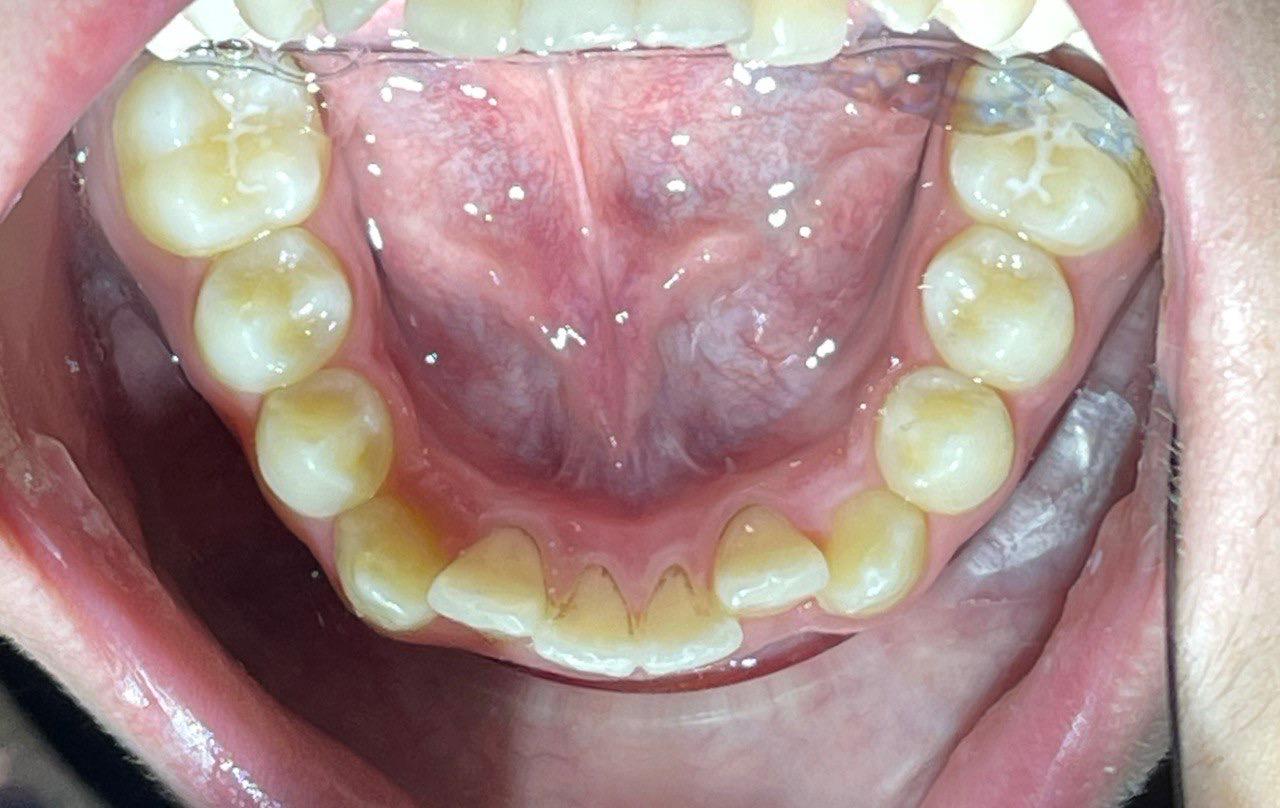

Выявленные проблемы

• Дистальная окклюзия ||(2)

• Глубокое резцовое соотношение

• Скученность фронтальных зубов

• Вестибулярное положение клыков

Брекет-система Ultra